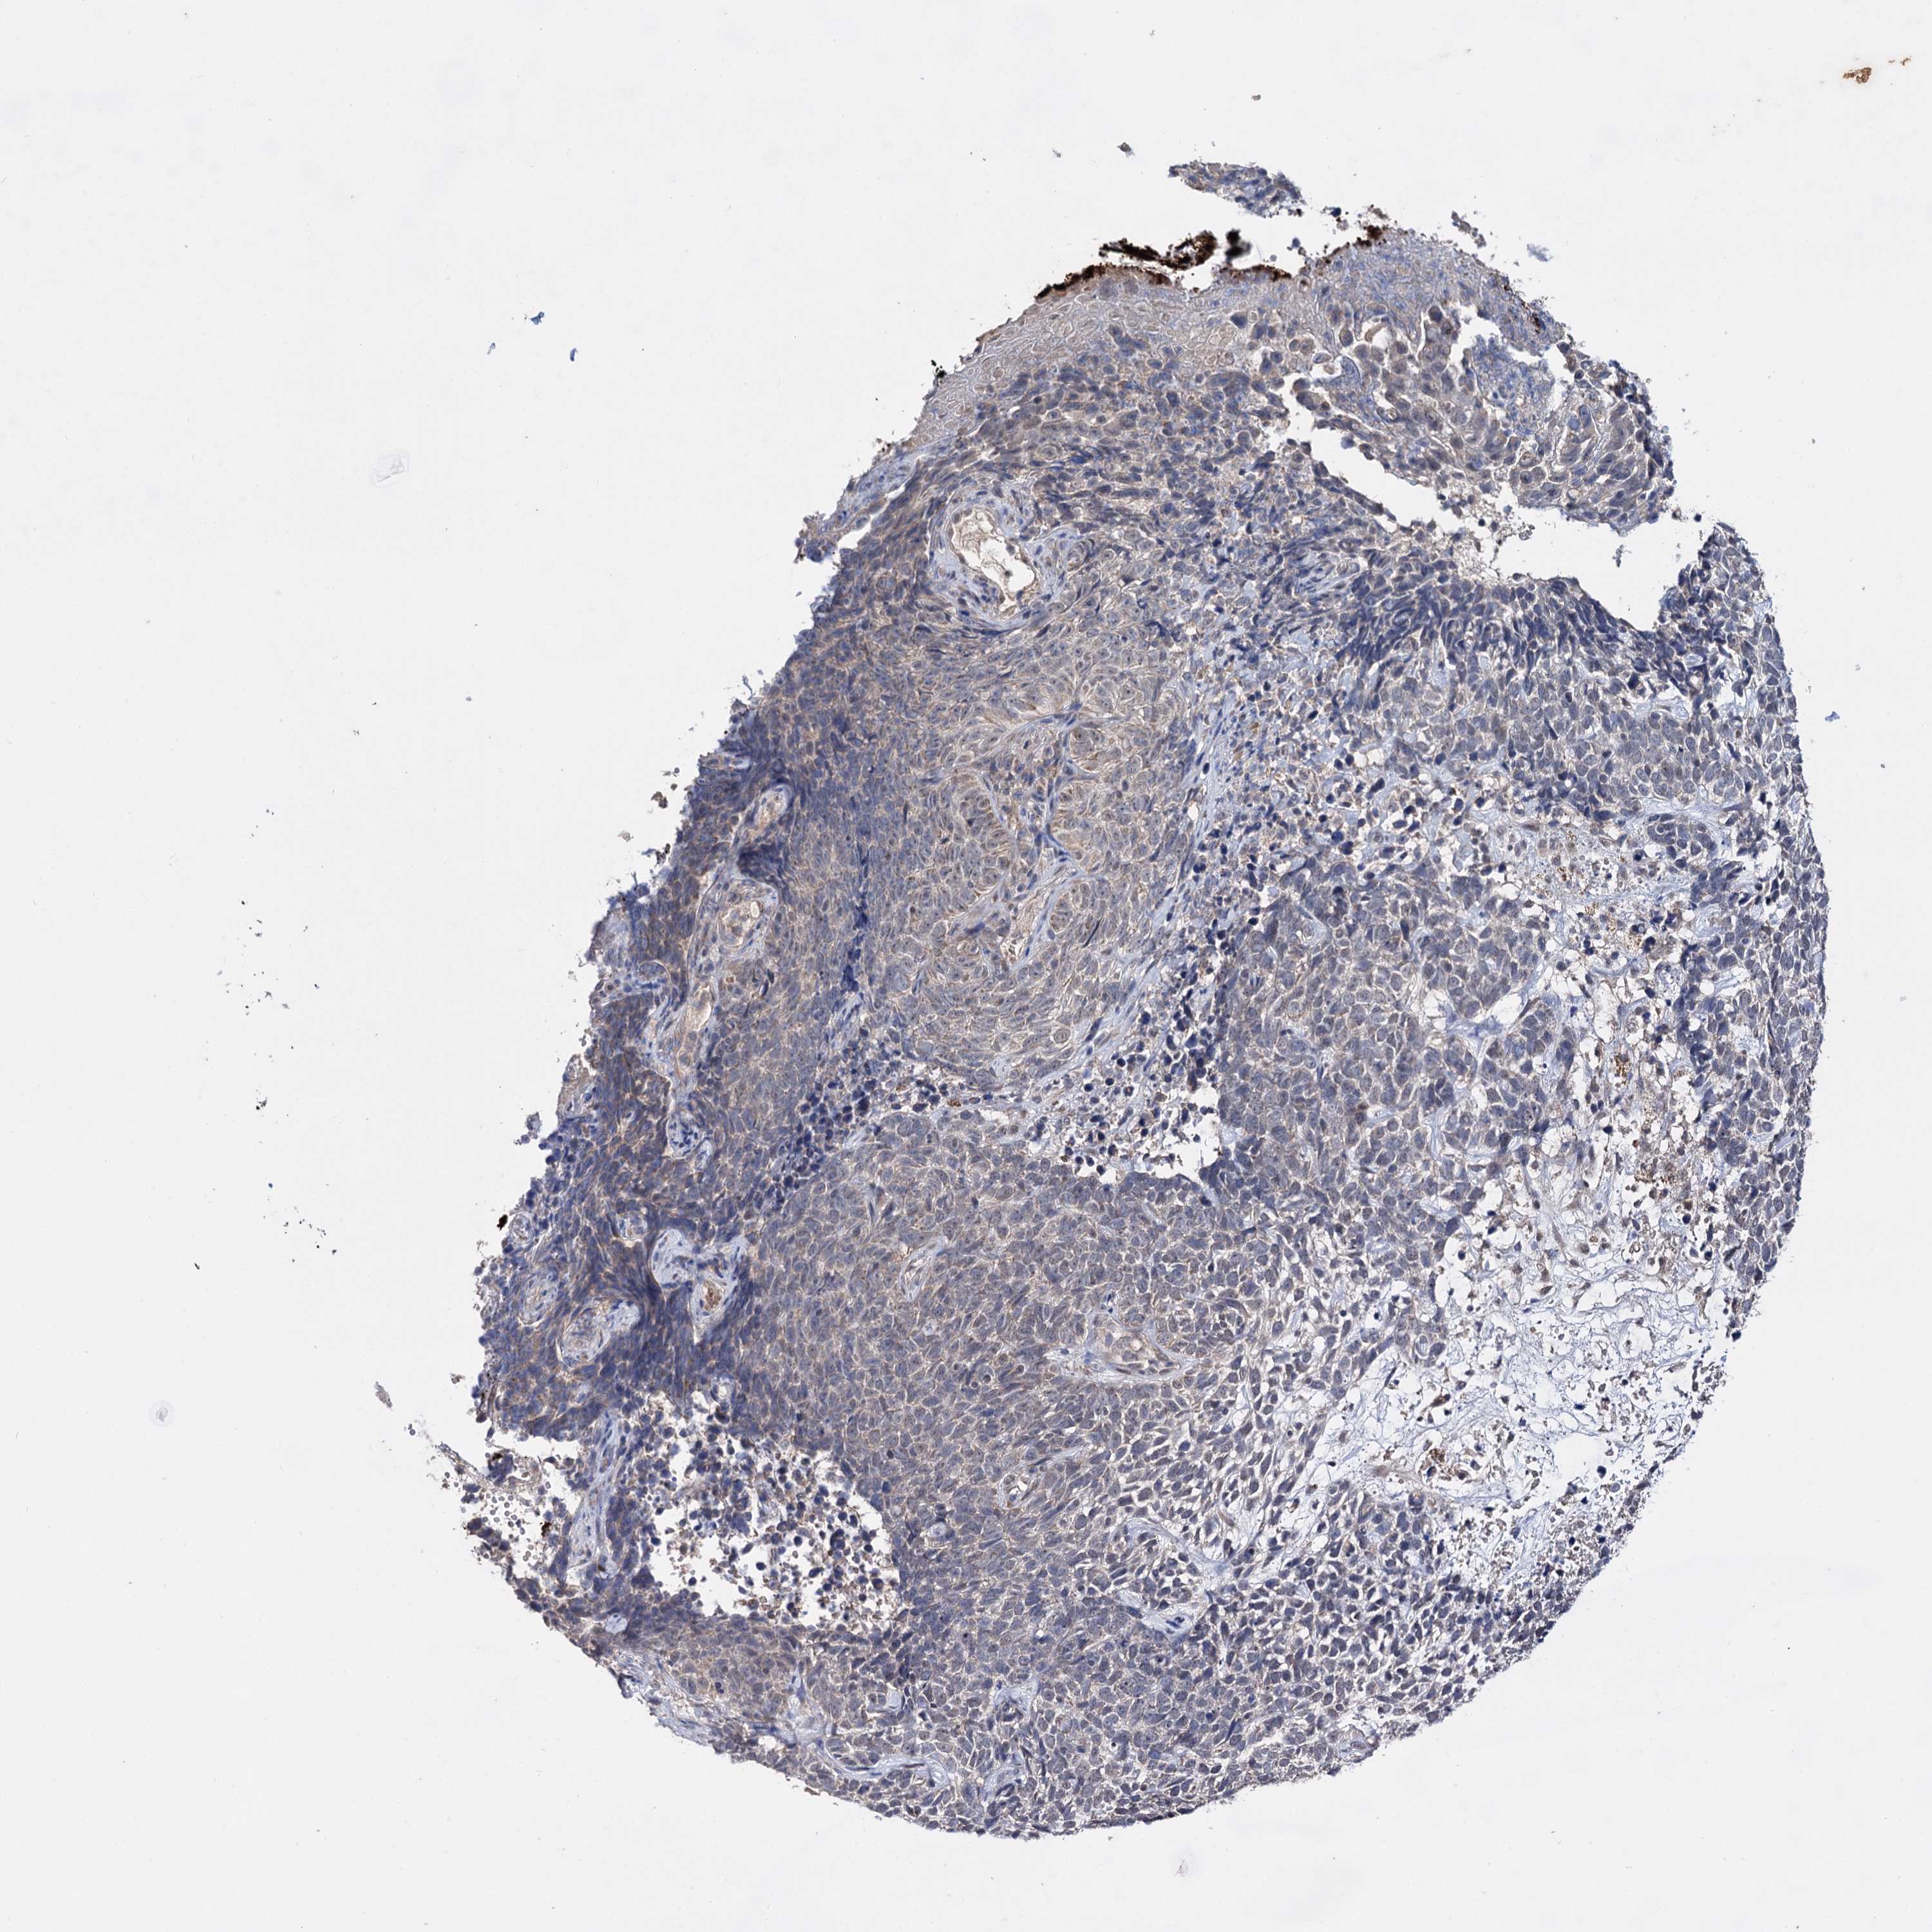

CANCER SKIN CANCER Show tissue menu

SKIN CANCER - Protein expressioni

A mouse-over function shows sample information and annotation data. Click on an image to view it in a full screen mode. Samples can be filtered based on level of antibody staining by selecting one or several of the following categories: high, medium, low and not detected. The assay and annotation is described here.

Each image is clickable and will lead to virtual microscopy that enables deeper exploration of all samples and also displays staining intensity scores, fraction scores and subcellular localization as well as patient and tissue information for each sample.

Antibody HPA039006

Squamous cell carcinoma, NOS